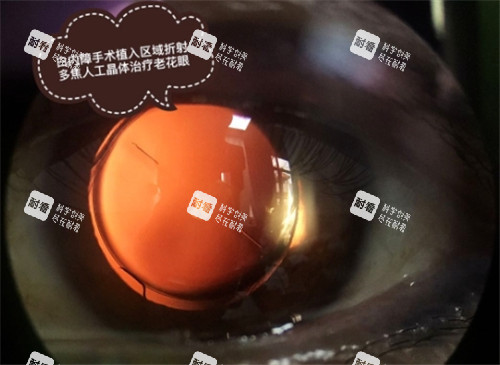

设备配置:引进德国蔡司全飞秒激光系统、美国爱尔康超乳玻切一体机等国内外一线设备,白内障手术精度达微米级;

医生团队:由杨明院长领衔的12人医师组,平均从业年限超15年,累计完成白内障手术超3万例,复杂病例处理经验充足;

手术方案:针对不同患者需求提供个性化选择,如单焦点晶体满足基础视觉需求,多焦点晶体实现远中近全程清晰视力。